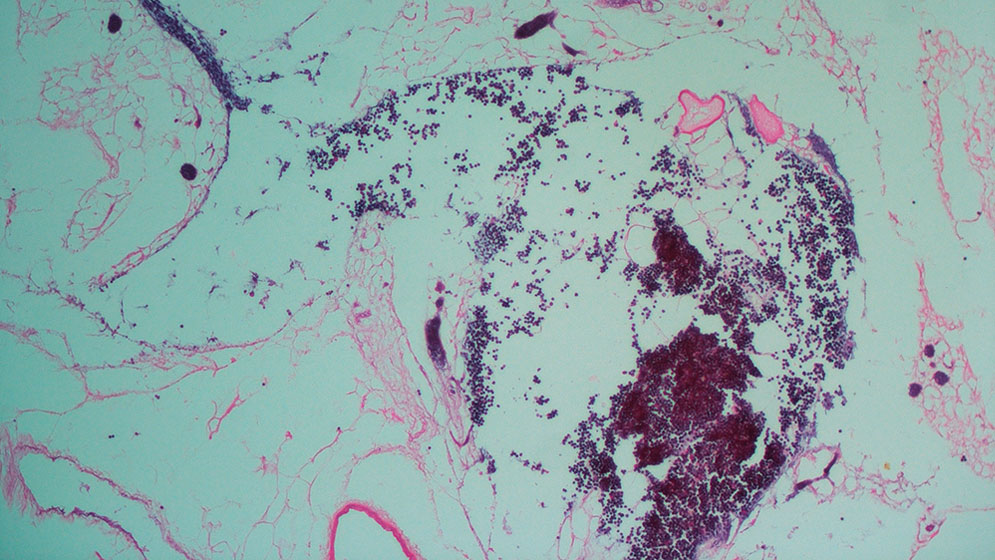

“Tras la cirugía se observó la correcta perfusión del órgano y la producción de orina. A través del microscopio se pudo observar la recelularización del órgano por parte de las células endoteliales humanas, que previamente habían sido marcadas con una proteína verde fluorescente (GFP, por sus siglas en inglés)”, explica Geraldine Haeublein, becaria doctoral del CONICET y primera autora del estudio.